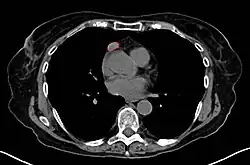

Imaging

A chest X-ray may identify widening of the mediastinum suggestive of thymoma, but computed tomography or magnetic resonance imaging (MRI) are more sensitive ways to identify thymomas and are generally done for this reason.[71] MRI of the cranium and orbits may also be performed to exclude compressive and inflammatory lesions of the cranial nerves and ocular muscles.[72]

As thymomas are seen in 10% of all people with the MG, they are often given a chest X-ray and CT scan to evaluate their need for surgical removal of their thymus glands and any cancerous tissue that may be present.[24][70] Even if surgery is performed to remove a thymoma, it generally does not lead to the remission of MG.[105] Surgery in the case of MG involves the removal of the thymus, although in 2013, no clear benefit was indicated except in the presence of a thymoma.[112] A 2016 randomized, controlled trial, however, found some benefits.[113]